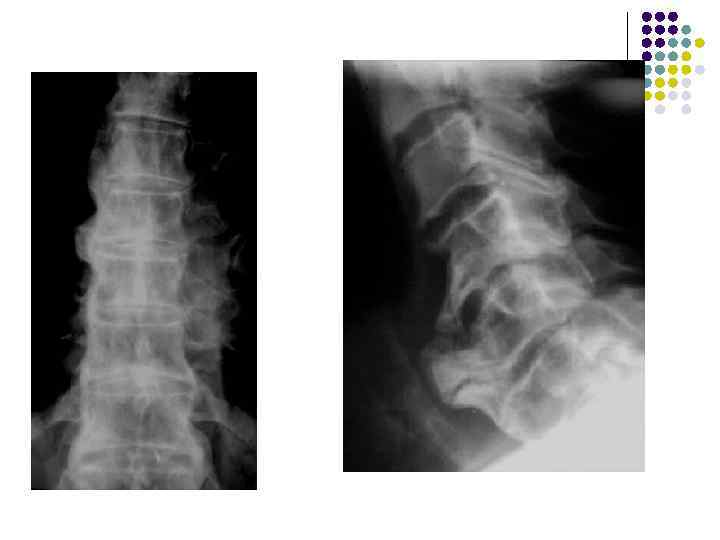

Остеохондроз Чаще развивается в L 4 -5 и C 5 -6. Шморль выделил под названием «хондроз» 1 стадию заболевания, когда патологический процесс ограничивается диском, а термином «остеохондроз» он обозначил II стадию.

Хондроз (по П. Л. Жаркову) 1. 2. 3. 4. Дистрофические изменения желатинозного ядра и фиброзного кольца Скошенная форма передних отделов тел позвонков, обусловленная выпячиванием межпозвонкового диска – атрофия от давления Функциональные пробы – высота диска не меняется Уменьшение высоты межпозвоночного диска Смещение позвонка (переднее, заднее, боковое) выявленное при съемке в вертикальном положении.

5. 6. 7. Нестабильное смещение позвонка при функциональном исследовании Сохранение четких непрерывных контуров всех поверхностей тел позвонков, отсутствие в них деструкции Локальное нарушение формы позвоночного столба на уровне измененного диска – выпрямление лордоза

Остеохондроз 1. 2. 3. 4. Кроме почти всех или всех признаков хондроза должны быть обязательно: Краевые специфические костные разрастания – вдоль выпяченного межпозвонкового диска (увеличение площади опоры) Уменьшение высоты межпозвонкового диска Субхондральный остеосклероз (выявить не легко) Сохранение четких непрерывных контуров всех поверхностей тел позвонков.

Стадии остеохондроза (по А. А. Скоромцу и Ю. Н. Задворнову) l 1 стадия – а) выпрямление лордоза, б) скошенность передне-верхнего края тела позвонка в боковой проекции в) деформация одного или двух полулунных отростков верхушки которых заострены или отклонены кнаружи; верхушка отростка склерозирована г) незначительное снижение межпозвоночного диска (может быть)

l l l 2 стадия а) деформация полулунных отростков более выражена, поражено большее их количество б) снижение высоты межпозвонкового диска в) субхондральный остеосклероз г) краевые костные разрастания